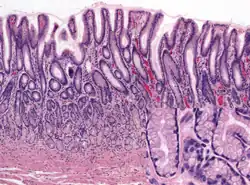

Glands

The mucosa lining the stomach is lined with gastric pits, which receive gastric juice, secreted by between 2 and 7 gastric glands. Gastric juice is an acidic fluid containing hydrochloric acid and digestive enzymes.[24] The glands contains a number of cells, with the function of the glands changing depending on their position within the stomach.

Within the body and fundus of the stomach lie the fundic glands. In general, these glands are lined by column-shaped cells that secrete a protective layer of mucus and bicarbonate. Additional cells present include parietal cells that secrete hydrochloric acid and intrinsic factor, chief cells that secrete pepsinogen (this is a precursor to pepsin- the highly acidic environment converts the pepsinogen to pepsin), and neuroendocrine cells that secrete serotonin.[25]

Glands differ where the stomach meets the esophagus and near the pylorus.[26] Near the gastroesophageal junction lie cardiac glands, which primarily secrete mucus.[25] They are fewer in number than the other gastric glands and are more shallowly positioned in the mucosa. There are two kinds - either simple tubular glands with short ducts or compound racemose resembling the duodenal Brunner's glands. Near the pylorus lie pyloric glands located in the antrum of the pylorus. They secrete mucus, as well as gastrin produced by their G cells.[27]